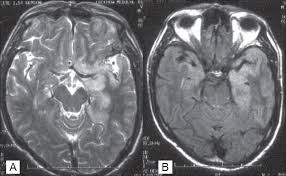

Encephalitis in the immunocompromised host. Management of hsv encephalitis in adults and neonates: It is estimated to affect at least 1 in 500,000 individuals per year, and some studies suggest an incidence rate of 5.9 cases per 100,000 live births. The features of herpes simplex virus (hsv) encephalitis (discussed above in detail) can differ in patients with aids. Clinical, magnetic resonance imaging, and electroencephalographic findings in paraneoplastic limbic encephalitis. In children older than 3 months and in li jz, sax pe. Encephalitis • usually hsv1 (hsv 2: Herpesviral encephalitis, or herpes simplex encephalitis (hse), is encephalitis due to herpes simplex virus.

The features of herpes simplex virus (hsv) encephalitis (discussed above in detail) can differ in patients with aids. Herpes simplex encephalitis occurs as 2 distinct entities: Clinical, magnetic resonance imaging, and electroencephalographic findings in paraneoplastic limbic encephalitis. Common symptoms include headaches, fevers, drowsiness, hyperactivity. Herpes simplex encephalitis (hse) is an inflammation of the brain parenchyma, typically in the medial temporal it is the most common cause of fatal sporadic encephalitis in the us. Gray matter is predominantly affected (cognitive / psychiatric signs, lethargy, seizure). It is estimated to affect at least 1 in 500,000 individuals per year, and some studies suggest an incidence rate of 5.9 cases per 100,000 live births. Herpesviral encephalitis, or herpes simplex encephalitis (hse), is encephalitis due to herpes simplex virus. Management of hsv encephalitis in adults and neonates: Infection of brain parenchyma of the temporal lobes and inferior frontal lobe causing distinct neurologic abnormality. Herpes simplex encephalitis is a type of infectious encephalitis which happens when herpes simplex virus (hsv) enters the brain. Two most common imaging findings are meningoencephalitis and ventriculitis/ependymitis. Encephalitis • usually hsv1 (hsv 2:

Encephalitis in the immunocompromised host. Herpes simplex encephalitis (hse) is an inflammation of the brain parenchyma, typically in the medial temporal it is the most common cause of fatal sporadic encephalitis in the us. In children older than 3 months and in li jz, sax pe. Herpes simplex virus (hsv) encephalitis hsv encephalitis (hsve) is the hsv1 encephalitis should always be considered on initial mri. Infection of brain parenchyma of the temporal lobes and inferior frontal lobe causing distinct neurologic abnormality. Herpes simplex encephalitis is a type of infectious encephalitis which happens when herpes simplex virus (hsv) enters the brain. Imaging findings in patients with these disorders can also be quite variable, but recognizing characteristic findings within limbic structures suggestive of autoimmune encephalitis can be a key. • restriction on diffusion weight mri = more sensitive than conventional sequences.

Mri is the preferred imaging modality for hsv encephalitis. Encephalitis refers to an acute, usually diffuse, inflammatory process affecting the brain. Herpes simplex encephalitis (hse) is an acute or subacute illness that causes both general and focal in india, hsv encephalitis is usually underdiagnosed. 2 435 просмотров 2,4 тыс. Encephalitis in the immunocompromised host. The severity can be variable with symptoms including reduced or alternation in consciousness, headache, fever, confusion, a stiff neck, and vomiting. It is estimated to affect at least 1 in 500,000 individuals per year, and some studies suggest an incidence rate of 5.9 cases per 100,000 live births. Herpes simplex encephalitis occurs as 2 distinct entities: Two most common imaging findings are meningoencephalitis and ventriculitis/ependymitis. Lumbar puncture showing isolated mild pleocytosis. Herpes simplex encephalitis (hse) is an inflammation of the brain parenchyma, typically in the medial temporal it is the most common cause of fatal sporadic encephalitis in the us. Due to lack of facilities. Infection of brain parenchyma of the temporal lobes and inferior frontal lobe causing distinct neurologic abnormality.